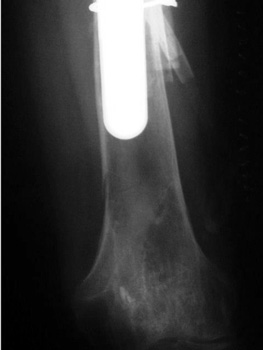

Long stem revised femoral component with periprosthetic fracture